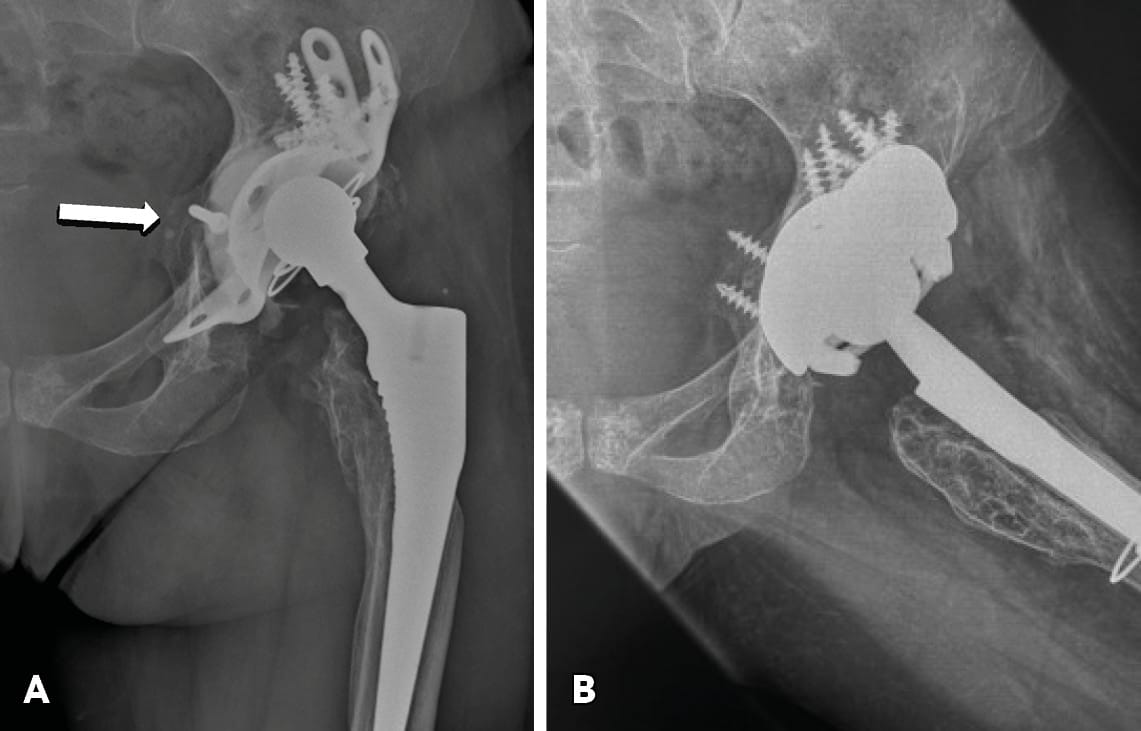

Cages and Rings with graft. Historically, massive bulk allograft, used with a cemented liner in the setting of severe bone defects had a 50% failure rate.[8] Garbuz D, Morsi E, Gross AE. Revision of the acetabular component of a total hip arthroplasty with a massive structural allograft. Study with a minimum five years follow up. J Bone Joint Surg Am. 1996; 78:693-697. In the past, reconstruction cages and rings have also been used extensively to reconstruct severe acetabular bone defects and PD. Structural or morsellised bone allografts were used in order to fill the acetabular defect and then a cage or ring was used to protect the grafted area until the allograft was incorporated by creeping substitution. Acetabular components were then cemented in an appropriate orientation. Several manufacturers have developed various ilioiscial (onlay or inlay) or non-ilioischial spanning cages and rings. However, despite reports of early satisfactory outcomes, many of these devices were later withdrawn due to subsequent mid- and long-term failures (Figure 5a).[9], Regis D, Sandri A, Bonetti I, Bortolami O, Bartolozzi P. A minimum of 10 year follow up of the Burch-Schneider cage and bulk allografts for the revision of pelvic discontinuity. J Arthroplasty. 2012; 27:1057-1063.e1.[10] Abolghasemian M, Tangsaraporn S, Drexler M, Barbuto R, Backstein D, Safir O, Kuzyk P, Gross A. The challenge of pelvic discontinuity: cup-cage reconstruction does better than conventional cages in mid-term. J Bone Joint Surg Br. 2014; 96-B(2):195-200.

Tantalum cementless acetabular cups with augments. TM and related (e.g. Cription) technology acetabular components fixed with multiple holes superiorly and inferiorly (ilium, pubic and ischial rami) in combination with augments have recently been used in severe acetabular defects and chronic PD, especially in those with good bone stock (Figure 5b).[14] Batuyong ED, Brock HS, Thiruvengadam N, Maloney WJ, Goodman SB, Huddleston JI. Outcome of porous tantalum acetabular components for Paprosky type III and IV defects. J Arthroplsty. 2014; 28: 1318-1322. Implants made of highly porous structural materials (e.g. Tantalum and Cription) have demonstrated an improved friction coefficient for initial stability and better bony ingrowth for late stability. Early and mid-term outcomes are encouraging, allowing for extending the indications for their use (Figure 6).[15] Jenkins DR, Odland AN, Sierra RJ, Janssen AD, Lewallen DG. Minimum dive year outcomes with porous tantalum acetabular cup and augment construct in complex revision total hip arthroplasty. J Bone Joint Surg Am. 2017; 99:e49.

Cup and cage construct. This technique involves the placement of a highly porous Tantalum jumbo acetabular cell or cup against the host bone, bridging the acetabular defect. On the top of the cell, a special inlay cage is placed which spans the defect and is fixed into the ilium and ischium.[16] Hanssen AD, Lewallen DG. Modular acetabular augments: composite void fillers. Orthopaedics. 2005; 28:971-972. Tantalum augments are also used when necessary. “Half” cup cage reconstruction (removing the distal flange from the “full” cup-cage construct in order to address technical problems with its distal insertion) has also been introduced.[17] Sculco PK, Ledford CK, Hanssen AD, Abdel MP, Lewallen DG. The evolution of the cup-cage technique for major acetabular defects: ull and half cup-cage reconstruction. J Bone Joint Surg Am. 2017; 99:1104-1110. Mid-term outcomes are favourable and this technique has gained in popularity.[18], Amenabar T, Rahman WA, Hetaimish BM, Kuzyk PR, Safir OA, Gross AE. Promising mid term results wit a cup and cage construct for large acetabular defects and pelvic discontinuity. Clin Orthop relat Res. 2016; 474:408-414.[19] Conan S, Dunscan CP, Masri BA, Garbuz DS. The cup-cage reconstruction for pelvic discontinuity has encouraging patient satisfaction and functional outcome at median 6 years follow up. Hip Int. 2017; 27(5):509-513.